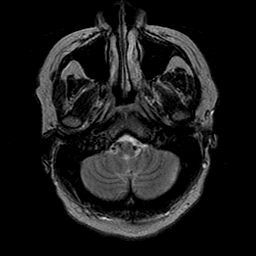

Cerebral hemorrhage, MR Study mr-t2 -- Slice #4

[Home][Help][Clinical] Slice 4